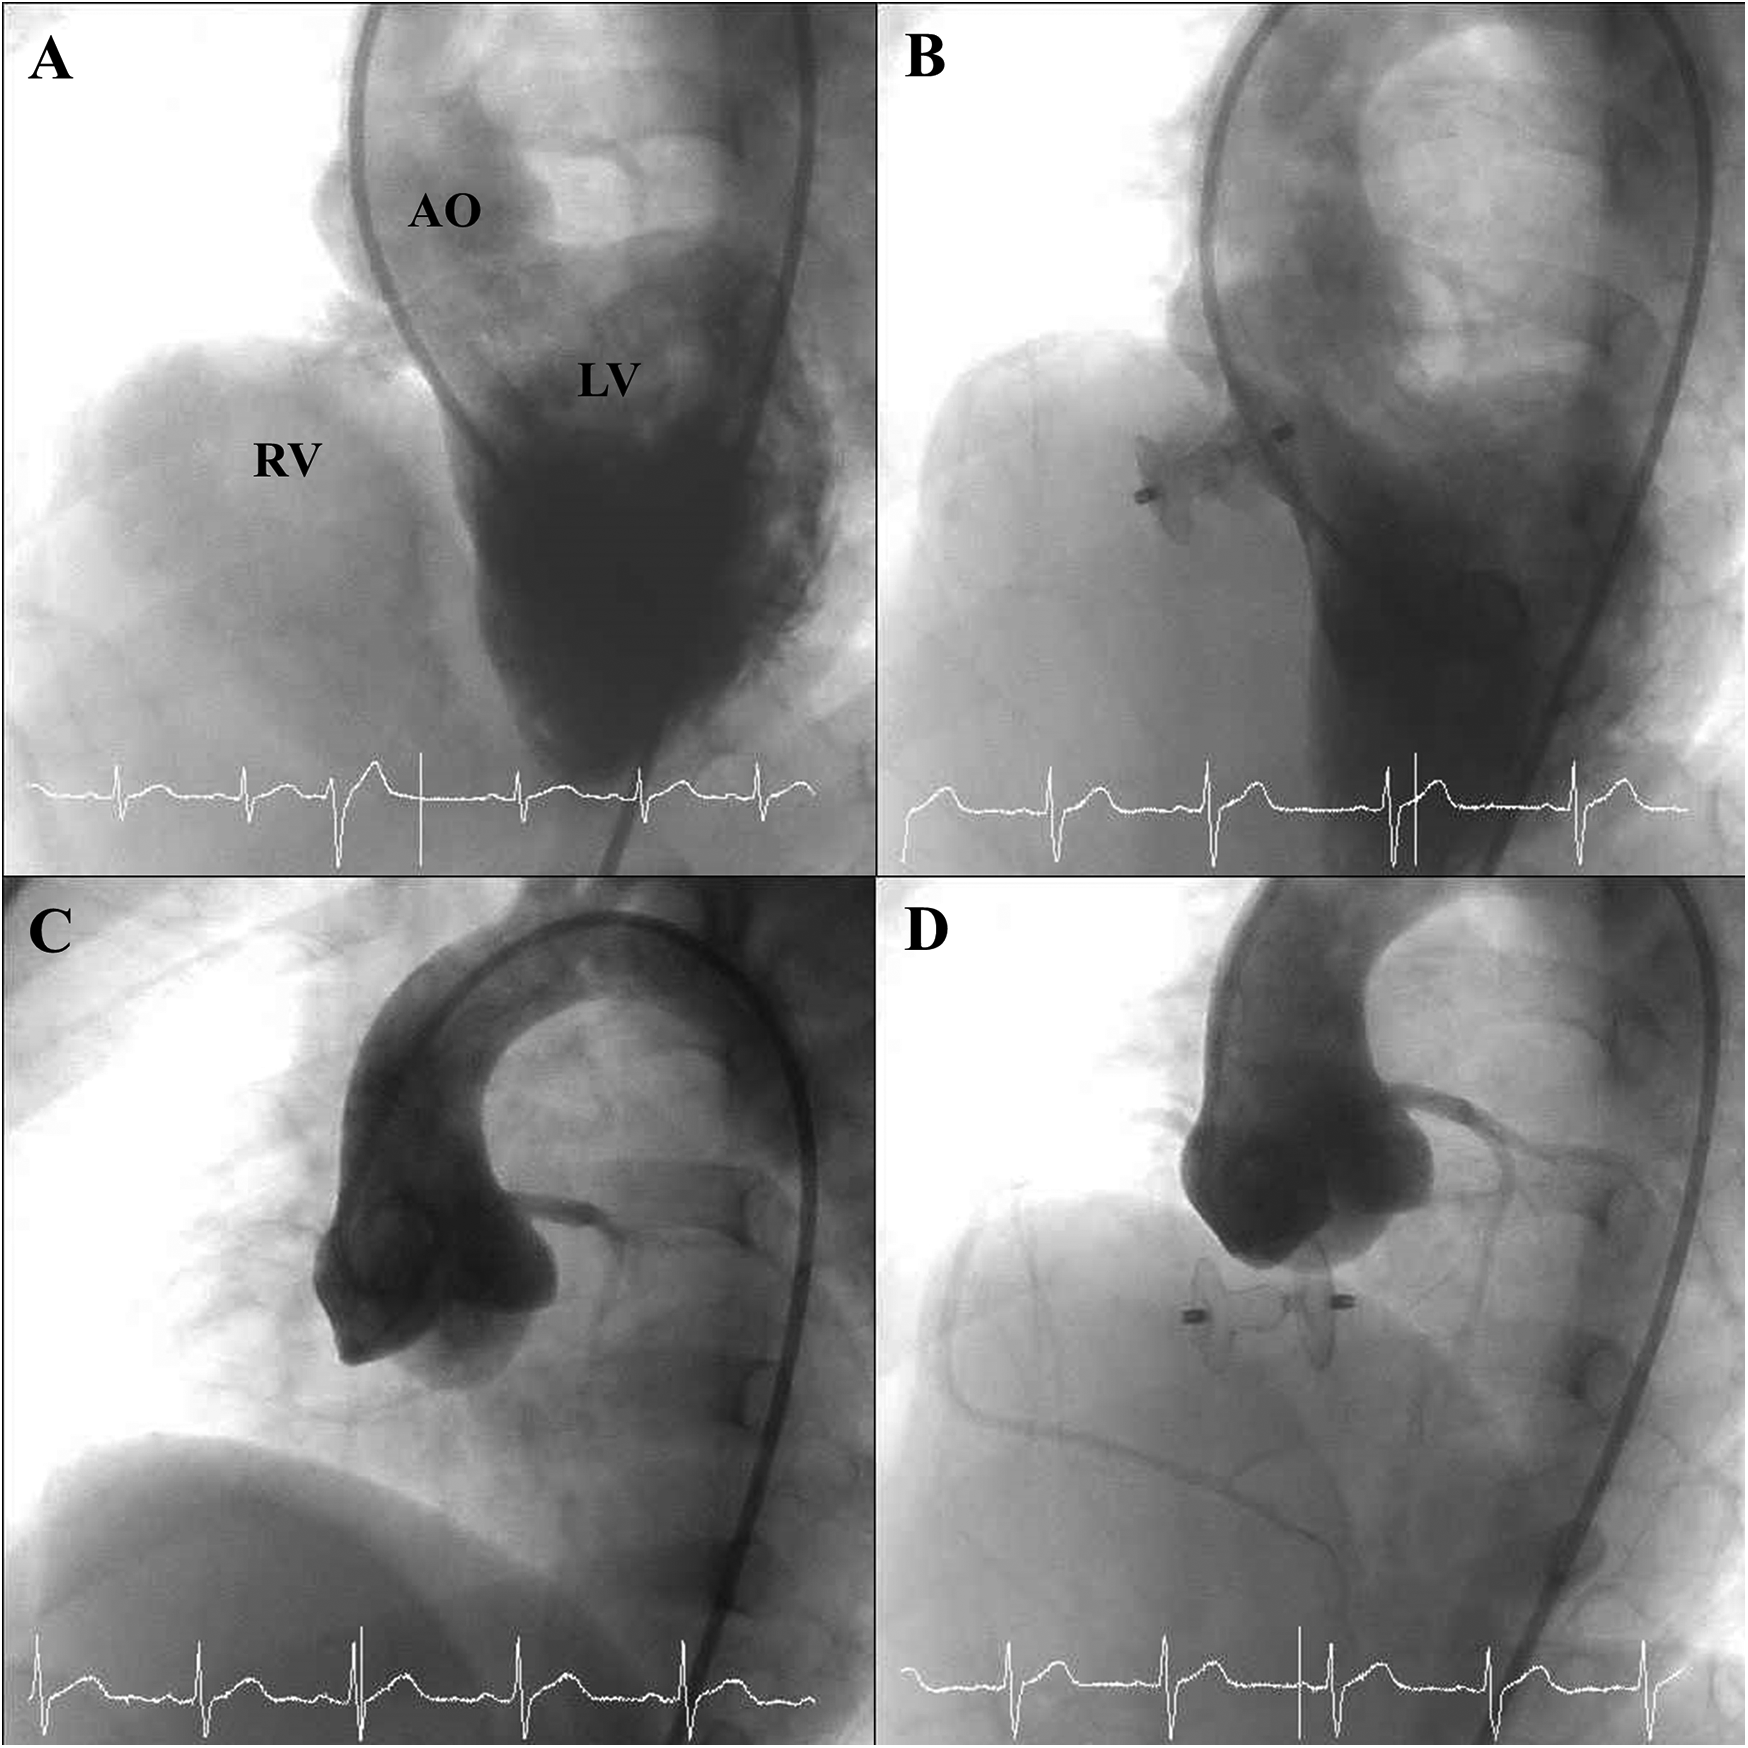

Closure indications included abundant shunting with Qp/Qs >1.5 (n = 48, 41.7%), mild AVP (n = 114), and failure to thrive (n = 71, 61.7%). Some had multiple indications. The median Qp/Qs ratio was 1.36 (IQR, 1.2–1.7), and the median mPAP was 17 mmHg (IQR, 14–20). Angiographic assessment before device implantation demonstrated PmVSD frequently accompanied by aneurysmal transformation of the membranous septum (Figure 1A) and, in most cases, mild AVP (Figure 1C). The median device size was 8 × 6 mm (range, 5 × 3 to 14 × 12 mm). The antegrade approach was initially attempted in 82 (71.3%) procedures and the retrograde approach in 33 (28.7%), with crossover in 11 procedures. The median procedure time was 62 min (IQR, 52–84), and the median fluoroscopy time was 22 min (IQR, 15–33) (Table 2). Post-deployment angiography confirmed successful device placement without interference with aortic valve function (Figure 1D), and no residual shunt was observed in the majority of cases (Figure 1B).

Figure 1

Angiographic findings before and after device deployment. (A) Pre-deployment angiographic image illustrating aneurysmal tissue of the membranous septum associated with the PmVSD. (B) Post-deployment angiographic view showing successful closure of the PmVSD without residual shunt. (C) Pre-deployment angiographic view demonstrating AVP associated with a PmVSD. (D) Post-deployment angiographic view showing persistent AVP in relation to the PmVSD, without interference from the occluder device.